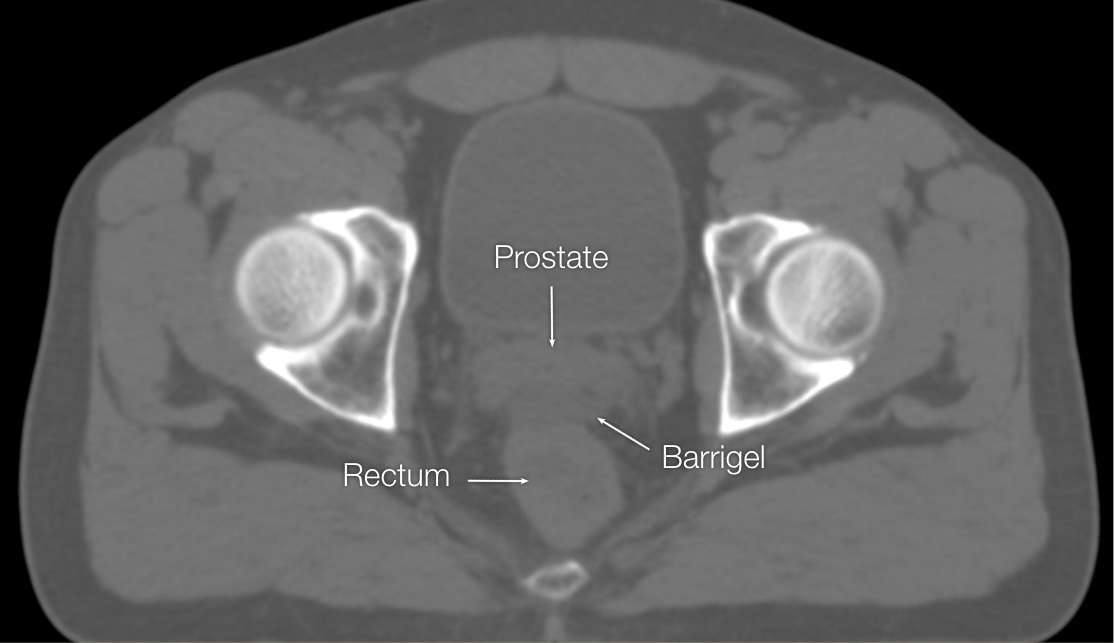

OPTIMIZING CT IMAGES

OPTIMIZING CT

IMAGES

Before (left) and after (right) adjusting window & level settings to enhance contrast and texture

CT images sourced from the Barrigel Pivotal Trial